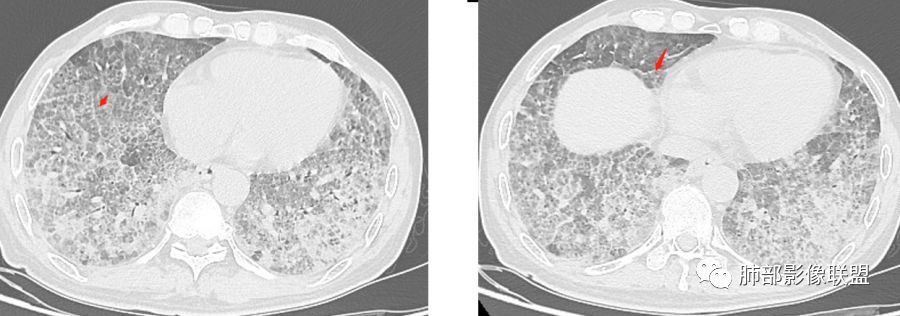

八爪:弥漫分布磨玻璃密度影,小叶间隔增厚,典型铺路石征,考虑PAP伴发感染性病变,鉴别特发性间质性肺炎,弥漫性腺癌,建议支气管灌洗;左肺上叶舌段不规则团片状阴影,显示不清,密切随访

小景:双肺弥漫磨玻璃影,小叶间隔增厚,呈碎石路征。患者粉尘接触史,考虑PAP。左肺舌段病灶,抗感染无吸收,腺癌待排。

长沟流月去无声:有职业性工作吸入史,但影像未见典型尘肺病表现(可能防护较好),中年男性,慢性咳喘,抗感染乏效,肿标CEA较显著升高,影像弥漫GGO+网格,全肺呈“铺路石征”,中下肺另有结节斑片影像。综合考虑:PAP和弥漫肺腺癌影像存在重合,病理确诊。

小赵:中老年男性患者。慢性病程,多次咳黄痰,治疗效果一般,反复发生。CT表现为双肺弥漫磨玻璃样改变,并呈细网格样铺路石状改变,上下肺无明显差异。双下肺为主多发渗出实变,边界不清,抗炎治疗后病变吸收不明显,局部似有进展。考虑肺泡蛋白沉积症基础上合并感染。肿瘤标志物高,中老年患者,肺炎型肺癌不除外。

碎石路征,下肺为主

1、GGO+网格——碎石路征

2、分布无特定位置,较随机

3、可有少许实变——部分与层厚有关

5、病灶较多时部分可见重力趋势

1.由于脂蛋白的沉积和占据,肺泡腔含气量减少,这是影像上较大范围“磨玻璃影”的基础。

2.由液体、细胞浸润和纤维组织造成的小叶间隔增厚是影像上多边形“铺路石征”的基础。

3.显眼的小叶间隔对病灶有阻挡作用是形成影像上“地图样改变”的基础。我们观察到的病灶与临近相对正常肺组织之间常常有比较清楚的分界。

4.病灶常多发,但心尖区及膈角区相对轻微。

5.部分病例显示有局部实变影